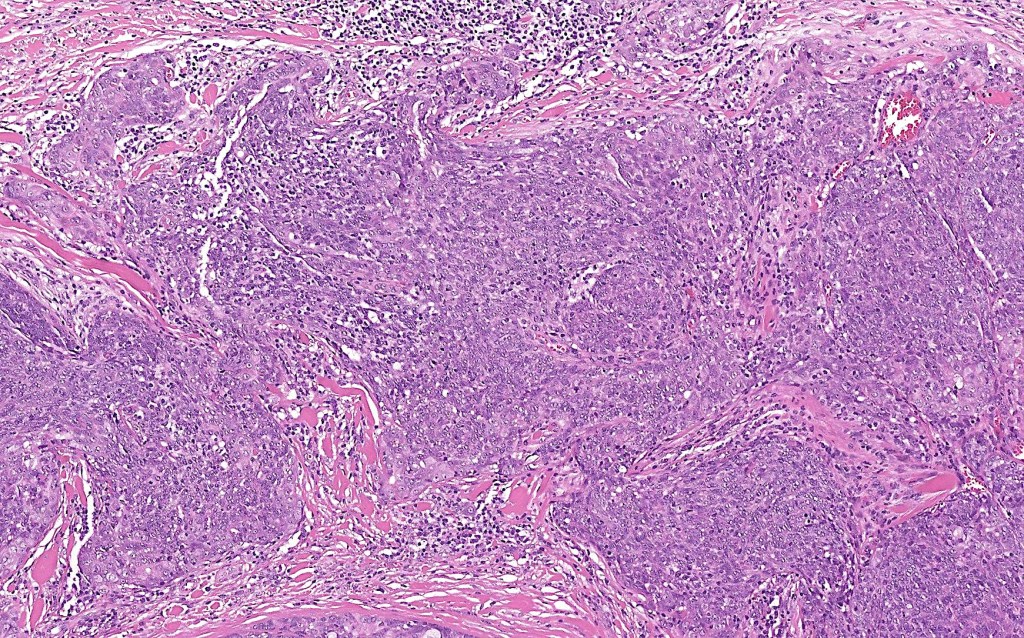

•Dermal generally circumscribed tumor nodule (less often it may show an infiltrative border)

•Syncytial epithelial component in nests, cords or sheets surrounded by an intense lymphoplasmacytic infiltrate

•Epithelial cells are large with abundant cytoplasm and vesicular nuclei with conspicuous nucleoli

•Marked mitotic activity, variable pleomorphism

•Absence of an epidermal connection